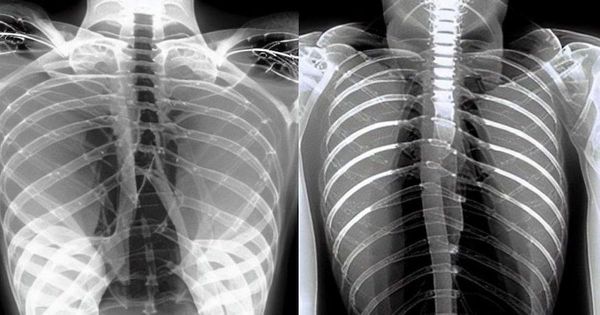

科学誌『Nature』で非常に広範な医療タスクを行えるジェネラリストな人工知能(AI)が提案された。患者とのやり取りによる情報収集から、医師の臨床での意思決定支援まで、広範に渡る応用を行うAIだ。AlphaFoldによるタンパク質の立体構造予測以来、医学界はAI応用の激流の中にいる。